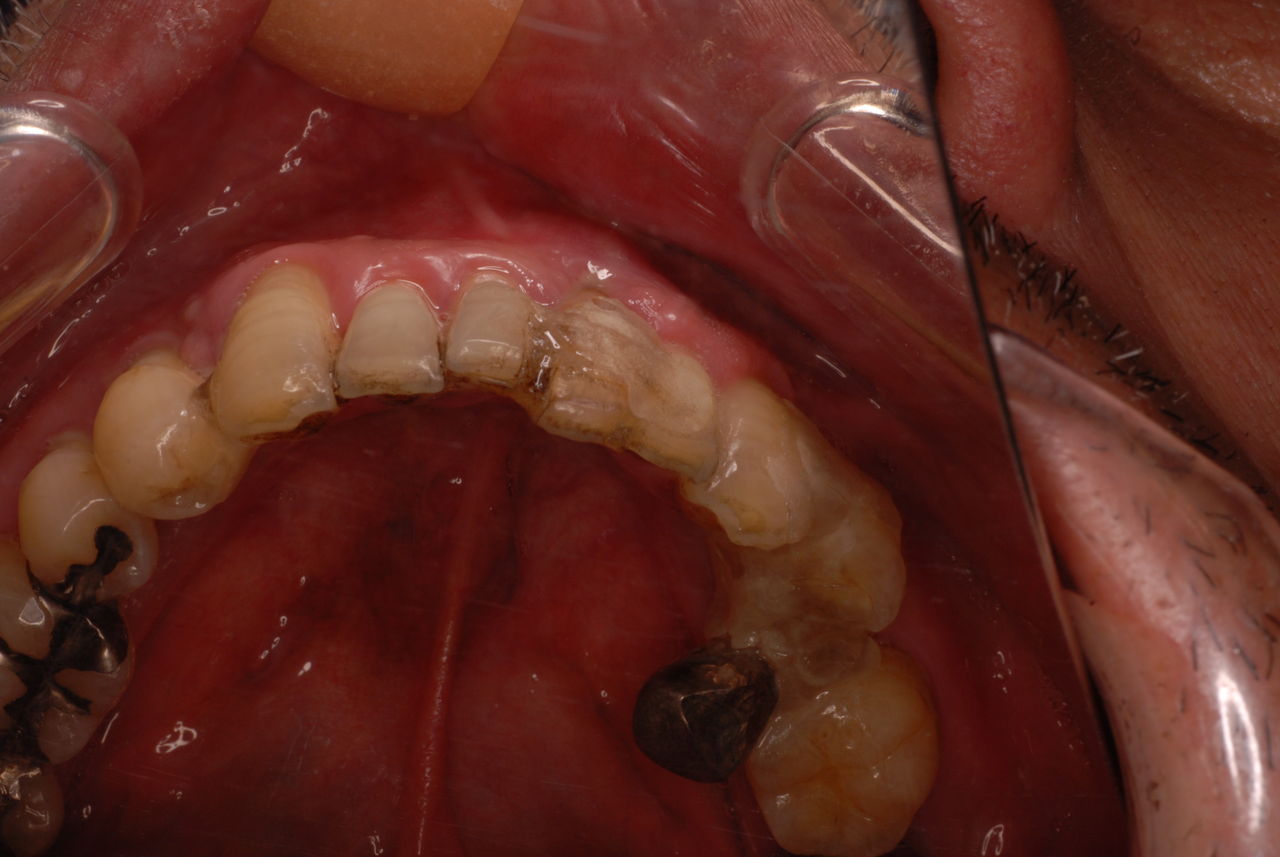

70代の患者ですが上の歯は残根一つ全て歯は無し。

下顎、殆ど歯はなく歯周病で抜けそうな歯と虫歯だらけの歯、適合の悪い銀歯が入っていてそれも虫歯と歯周病で危ない状態でした。入れ歯は下の入れ歯は入れたことがないようです。(ため息)痛くて入れたことがないそうです。

左下の歯は歯の中の治療も?ですごい歯周病を患い歯茎の穴(ポケットと呼ばれるところ)から膿が出ているのです。ばい菌と毒素で骨が溶けて深い穴ができてそこにまたバイキンと毒素がたまるという悪循環ができているのですね。

右下の歯は歯の中の治療もあやしいのですが、金属と歯の間がすでに虫歯で崩壊し始めています。

プラークというバイキンと毒素と食べかすの塊が歯の周りや歯茎にまとわりついて虫歯になり且つ重症の歯周病を患っています。